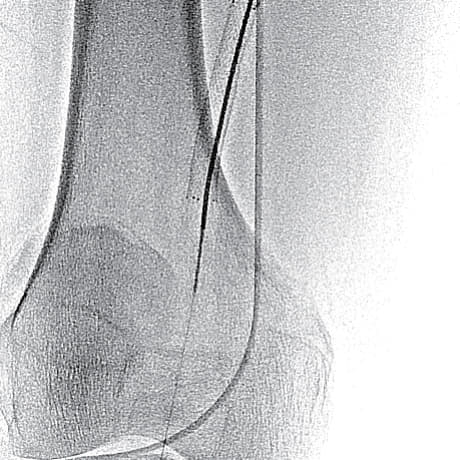

- ステント近位端のみではなく、遠位端やBMSとDESとの重複留置部の硬化が強く難渋したが、なんとか閉塞病変を通過(図3)